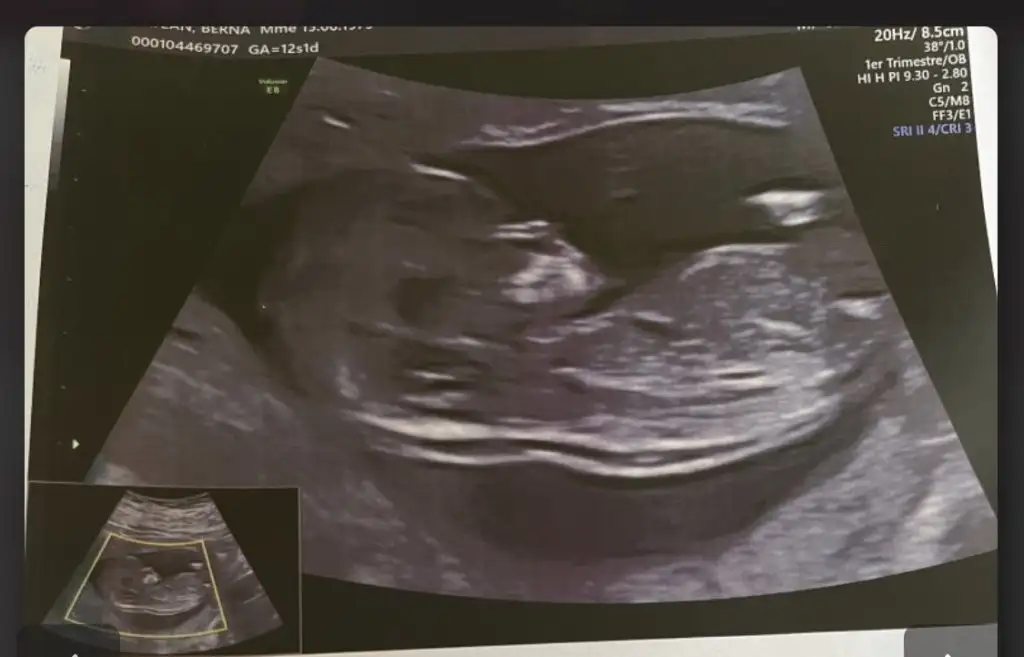

Cinsiyet tahmini

• BB4C0B06-24C8-47FE-AF5D-D3EA7BBD392F.webp

BB4C0B06-24C8-47FE-AF5D-D3EA7BBD392F.webp

19,9 KB · Görüntüleme: 38